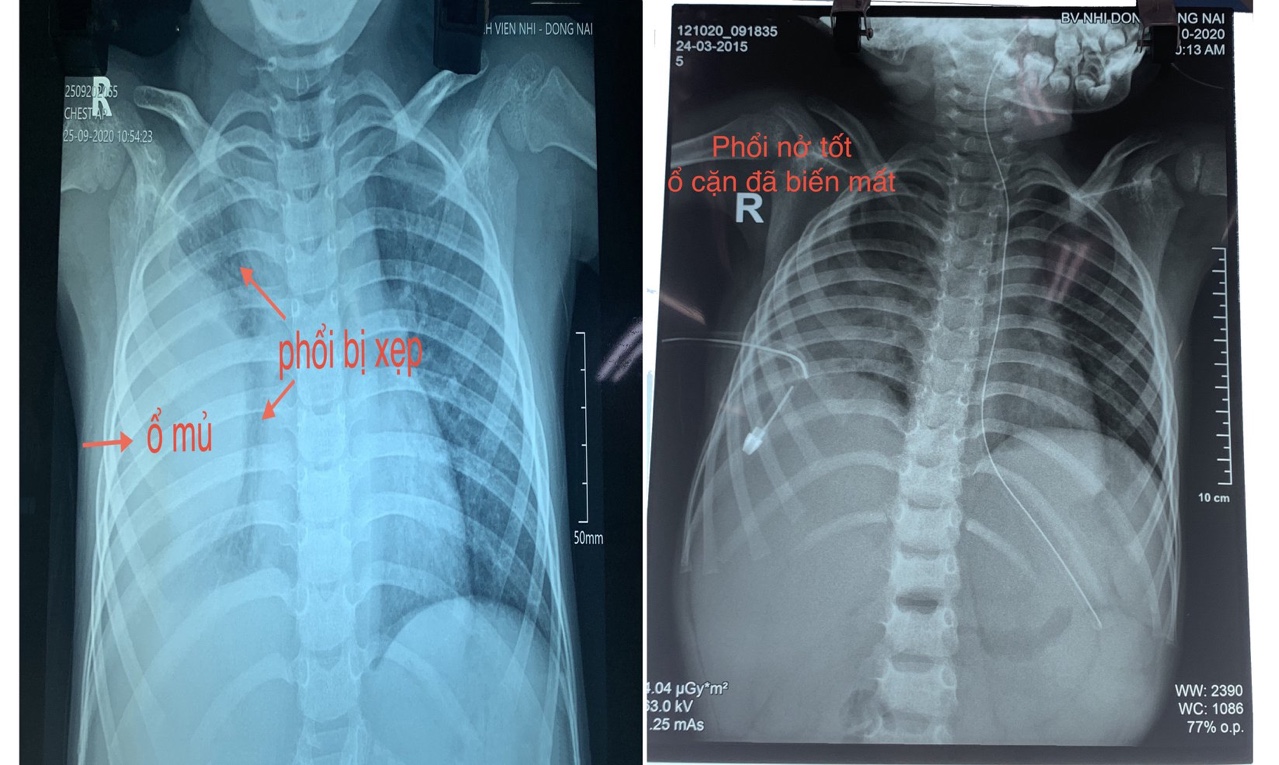

Phim chụp phổi của bệnh nhi trước và sau khi phẫu thuật

Các bác sĩ đã thăm khám, chụp X-Quang ngực cho bệnh nhân, ghi nhận tình trạng viêm phổi rất nặng kèm tràn dịch khoang màng phổi phải. Sau 12 ngày điều trị, tình trạng viêm phổi của bé đã ổn nhưng dịch mủ màng phổi vẫn còn. Do đó, các bác sĩ đã tiến hành hội chẩn ngoại khoa và quyết định sẽ phẫu thuật cho bé.

Tuy nhiên, các bác sĩ nhận định trường hợp này nếu mổ sẽ gặp nhiều khó khăn vì ổ cặn màng phổi đã bị vách hóa và rất dính với nhu mô phổi. Ngoài ra, vấn đề gây mê cũng gặp khó khăn về thông khí hạn chế do phổi phải của bé gần như đã bị xẹp hoàn toàn. Sau khi hội chẩn với các bác sĩ Bệnh viện Nhi đồng 2 TP.HCM, ê kíp phẫu thuật lồng ngực của Bệnh viện Nhi đồng 2 TP.HCM gồm phẫu thuật viên, bác sĩ gây mê đã xuống Đồng Nai hỗ trợ các bác sĩ Bệnh viện Nhi đồng Đồng Nai. Sau 1 giờ đồng hồ, ca phẫu thuật thành công. 8 ngày sau mổ, tình trạng hô hấp của bé đã hồi phục rất tốt, ổ mủ màng phổi cơ bản được làm sạch, phổi nở tốt.